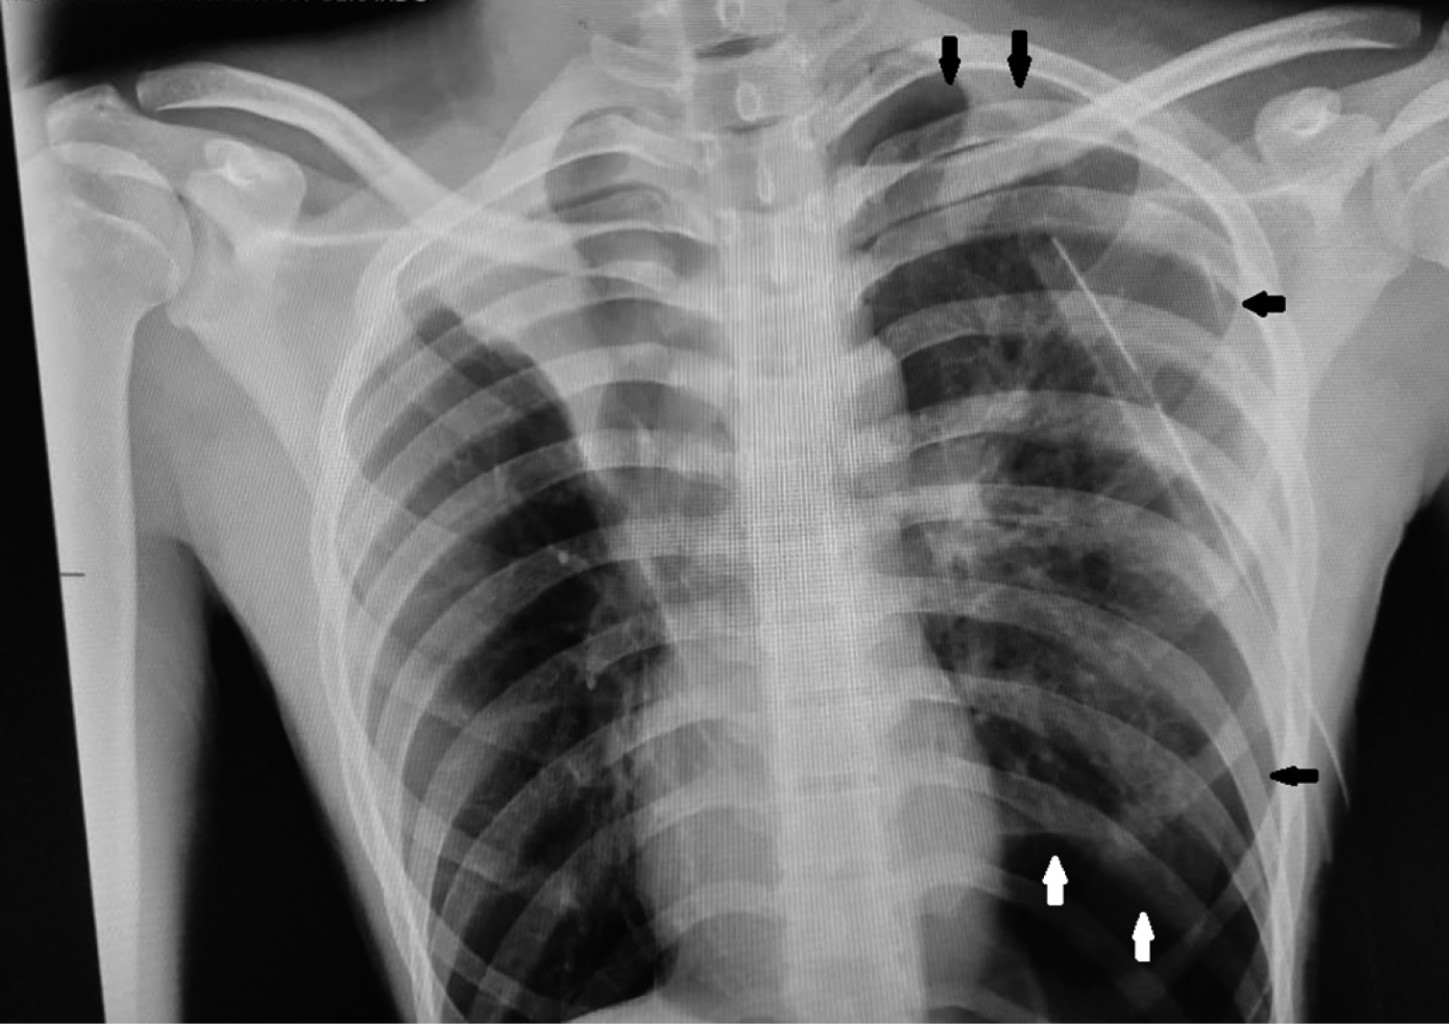

Tomografía: se observa neumotórax izquierdo, con presencia de sonda endopleural y bulla apical izquierda (Figura 4).

Figura 4